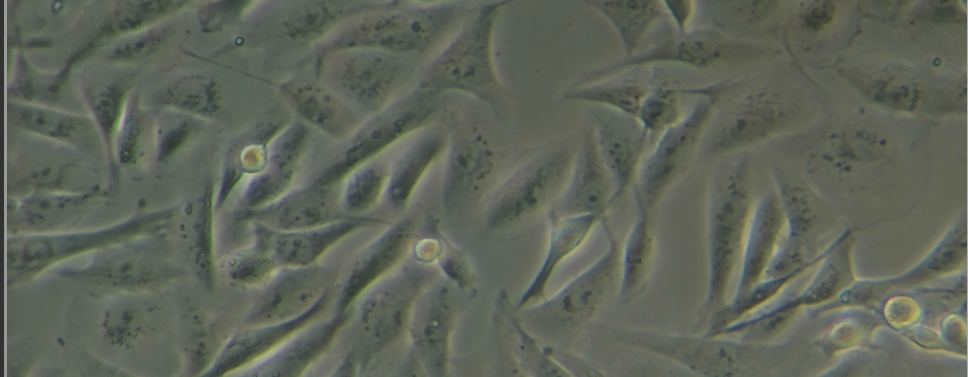

细胞形态

大部分为纺锤状,也有部分细胞呈圆形,贴壁生长,但会存在少量悬浮细胞。